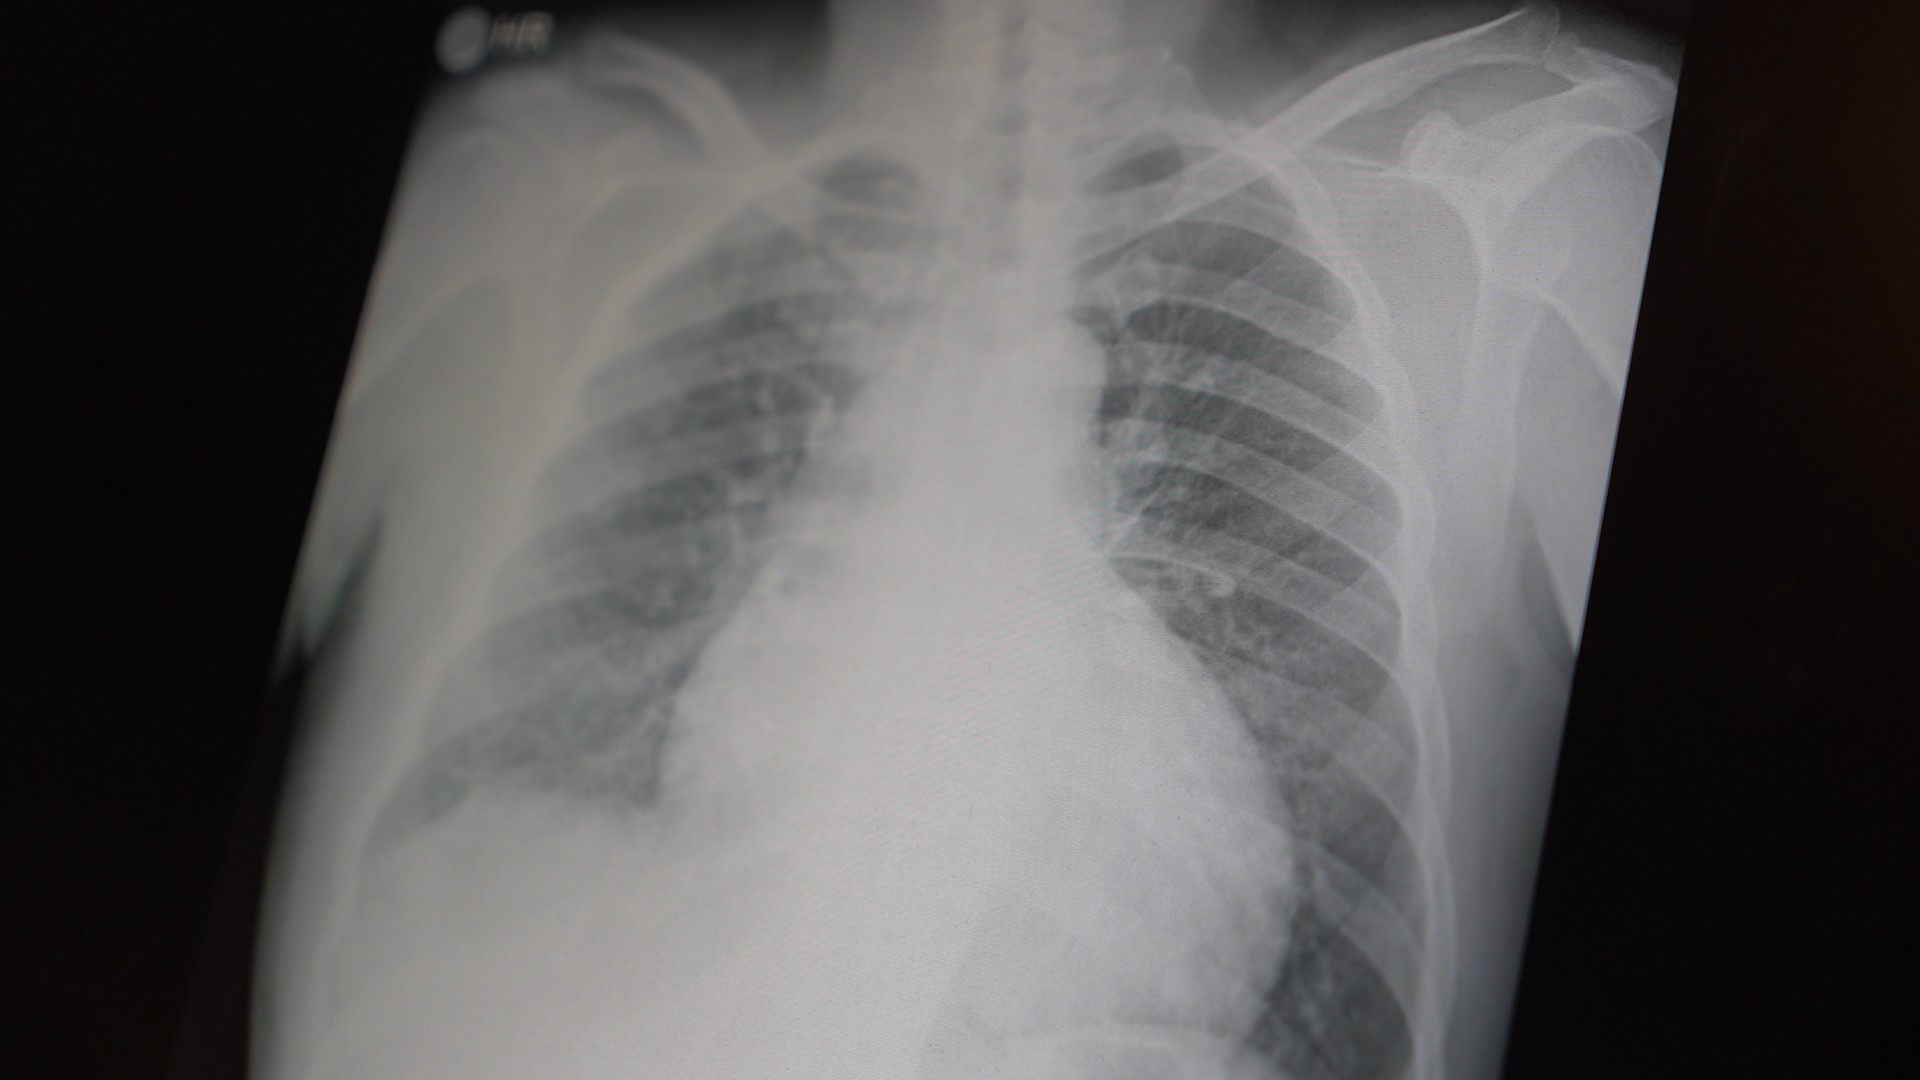

Tüm dünyada çocukları ve gençleri etkileyen iki önemli bağımlılıktan bahsetmek istiyorum. Bunlar metamfetamin ve kokain bağımlılığıdır. Metamfetamin en ölümcül, en çok bağımlılık yapan, okul çağında en kolay ulaşılabilen bir sentetik uyuşturucudur. Kullanıma bağlı ciddi akciğer ve karaciğer sorunları ortaya çıkıyor. Çok küçük dozlarda bile anında bağımlılık yapabiliyor ve tedaviyle bırakılması çok zor bir bağımlılıktır